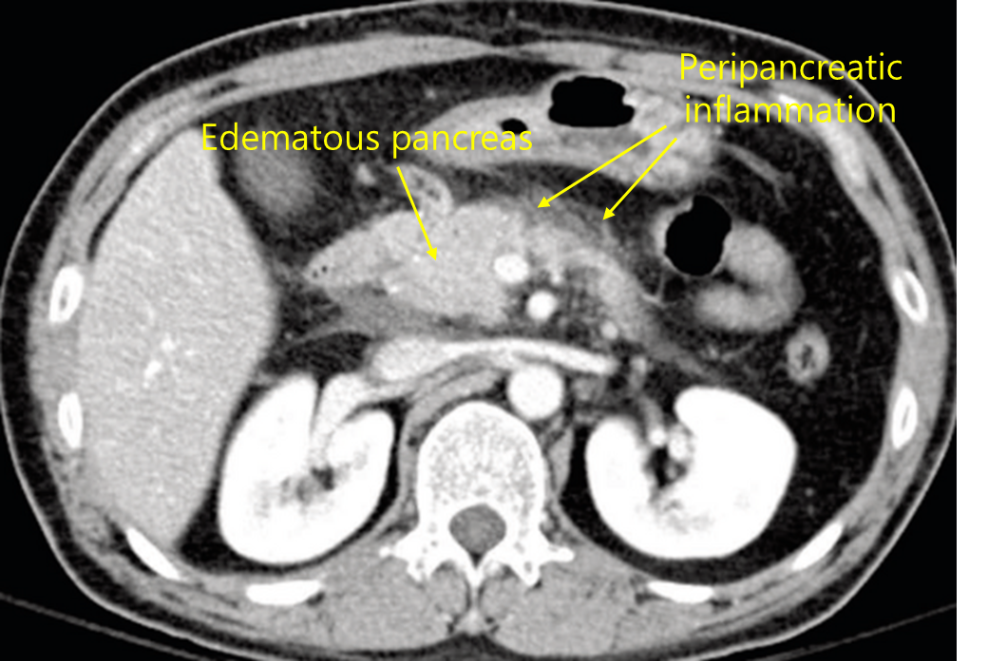

Img | CT: Edematous pancreas, with peripancreatic fluid collections |

• CT상 edematous한 pancreas와 pancreas 주변의 fluid collection이 확인되며, 이는 acute edematous pancreatitis에 합당한 영상 소견이다.